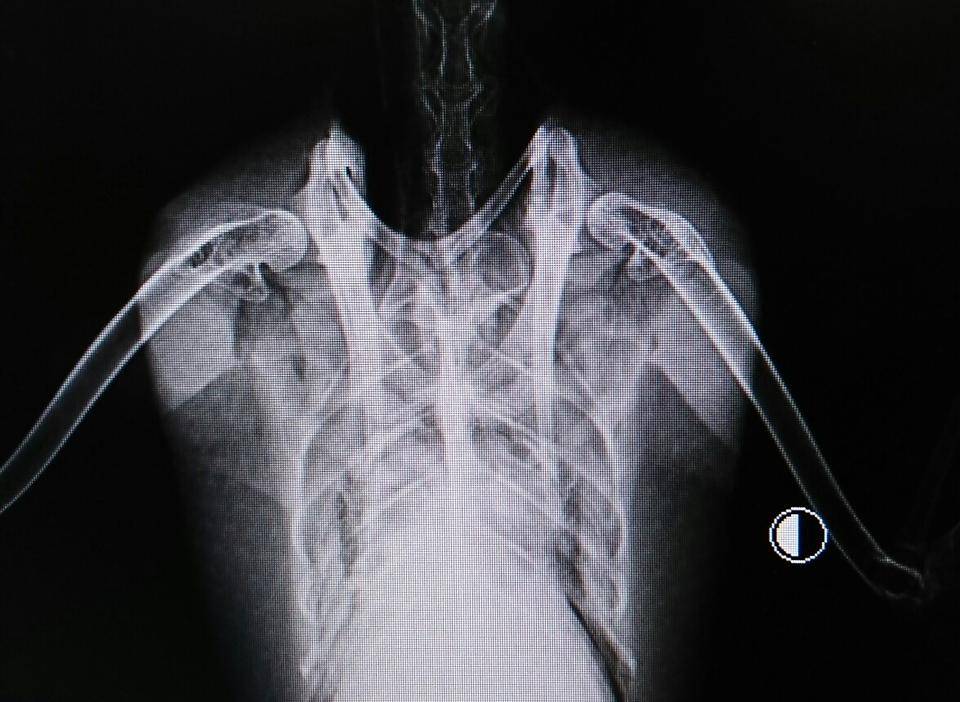

レントゲンを撮るのです。

ちょっとわかりにくいですが...

このレントゲンはメスです。